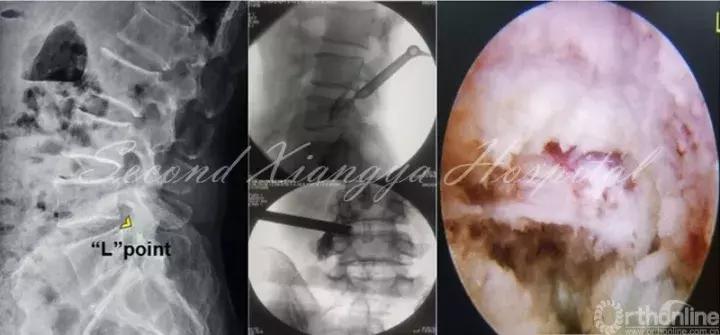

虽然上述三种技术有所不同,但术中定位均以骨性结构“L”点为标志是其共同特点。“L”点指的是上关节突基底部与椎体后上缘交接区,以此点来建立工作通道可以有效避开神经与血管结构,同时通过关节突成型扩大操作空间,从而完成安全减压操作。

椎间孔入路操作技巧应注意“关突引导,循骨而进,成型忌粗,遇痛即止。”也就是说,以上关节突为引导,沿着上关节突进入到硬膜外间隙,固定通道后,探及底面为硬性骨组织后,用环锯进行一次成型,成型后半过程如患者出现神经疼痛,应停止前进,术中并用透视证实成型工具末端不超过椎弓根内侧缘。

椎板间入路的靶点亦可以根据“L”点进行确定,“L”点指下椎板上缘和上关节突交接区,该部位也是侧隐窝骨性部分入口,显露黄韧带后,可以容易找到其下方的神经根,同时循神经根向肩部显露其全程,内侧黄韧带予以保留。“L”点确定为安全显露神经根提供良好的骨性标记。